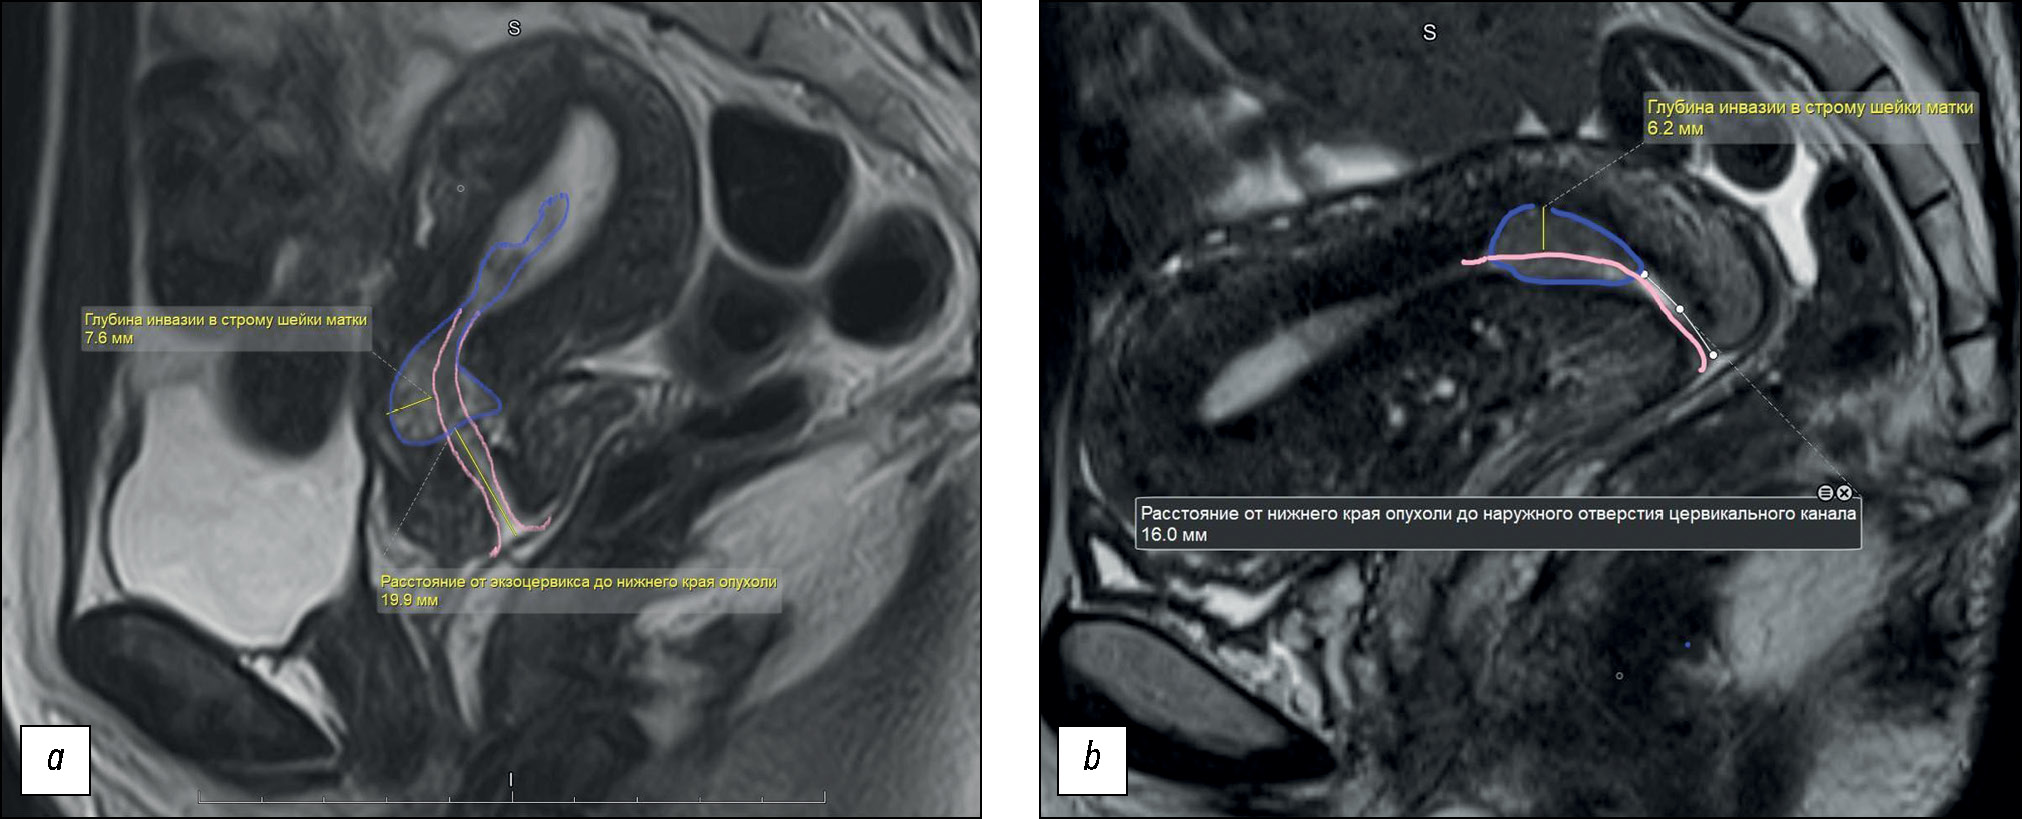

T2-WI MRI data were used to evaluate the size and depth of cervical stromal invasion (Fig. 2); the presence of parametrial invasion; involvement of the internal orifice and isthmus of the uterus, endometrial lining, uterine appendages, and lymph nodes; and the presence of a “feeding pedicle” in the tumor. The tumor pedicle was used to designate the junction between the tumor and uterine wall, considered as the tumor origin, with tumor feeding vessels visualized in the arterial and venous phases of dynamic contrast enhancement.

Fig. 2. An example of measuring the depth of cervical adenocarcinoma invasion into the stroma and the distance from the tumor to the exocervix: (а) the tumor is located in the upper third of the cervix, has a depth of invasion of 8 mm and is located at a distance of 20 mm from the exocervix; (b) the tumor is located in the upper third and middle third of the cervix, has a depth of invasion of 6 mm and is located at a distance of 16 mm from the exocervix. The tumor is outlined with a purple line, the endocervical canal is marked with pink lines. Conclusion of the pathomorphological study: endocervical adenocarcinoma of the cervix grade 2; depth of invasion into the cervical stroma 5 mm (less than 1/2 the thickness of the cervical wall); lymphovascular invasion was detected; the tumor grows into the internal os; endometrium in the secretion phase.